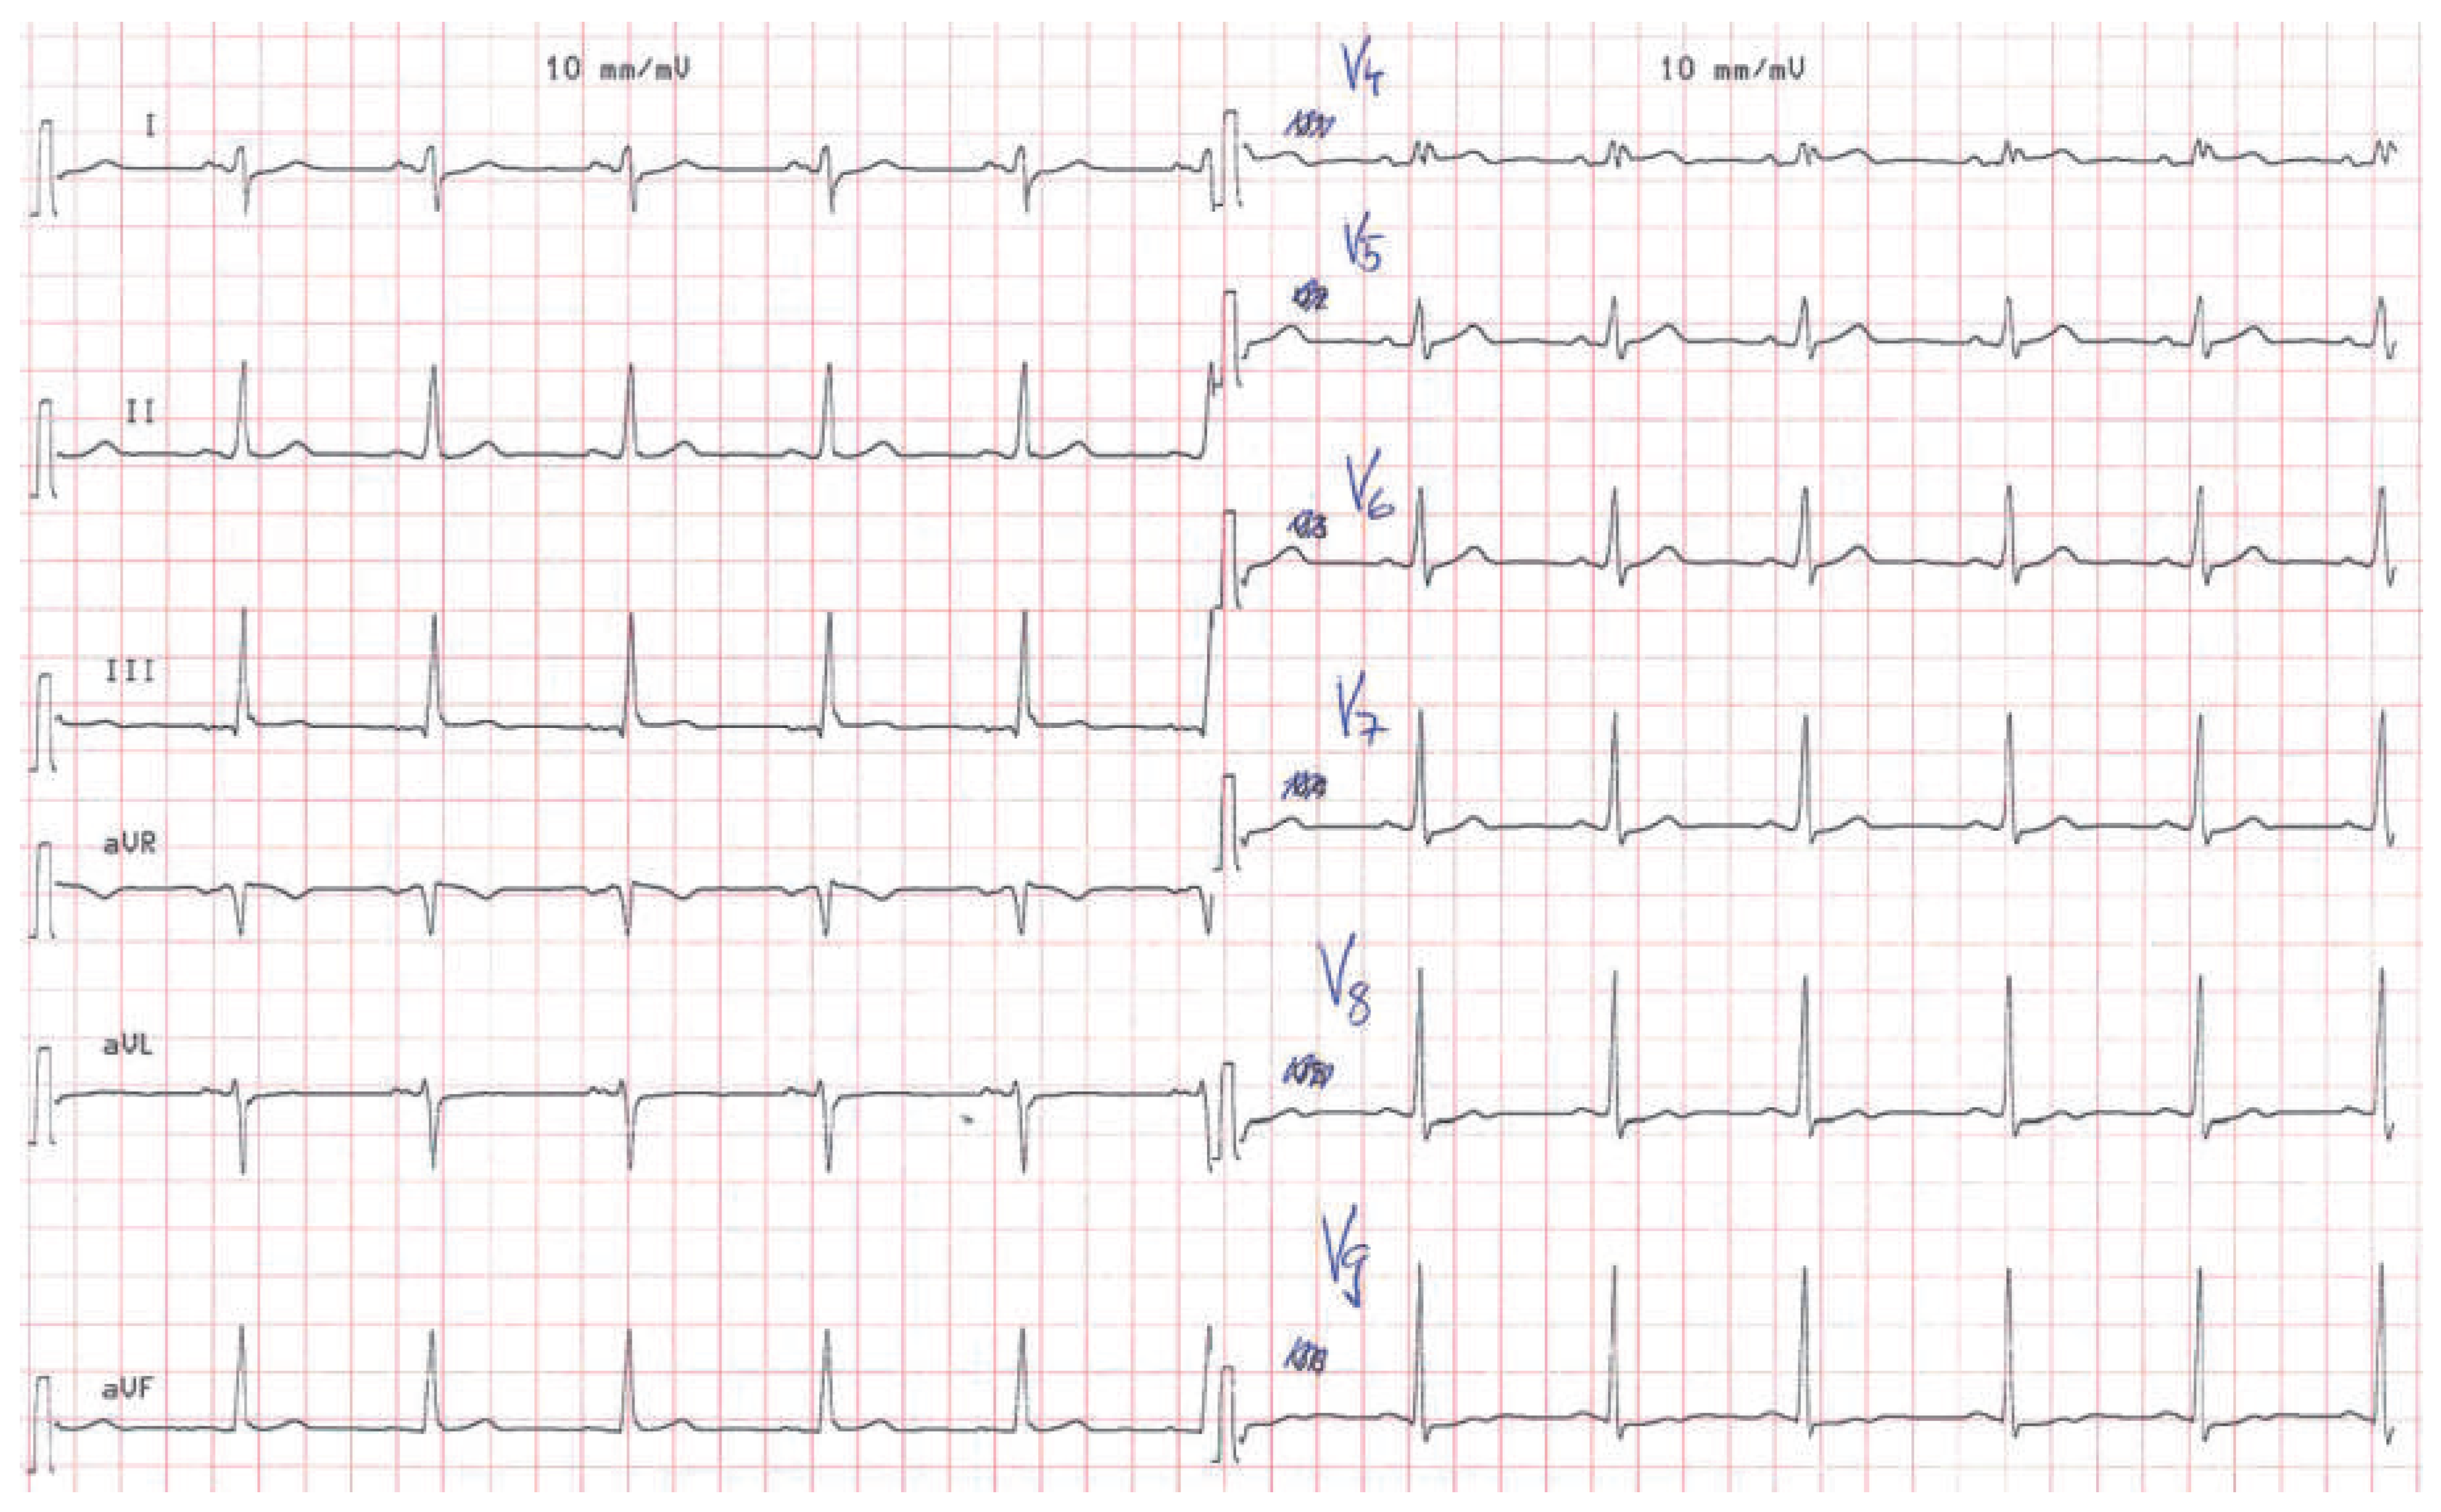

A 57-year-old male presented to the medical outpatient department with typical angina pectoris Canadian Cardiovascular Society (CCS) class II and dyspnoea on exertion during the previous weeks. Additionally he had retrosternal pain at rest and dyspnoea during the previous night. The patient had a a history of untreated arterial hypertension. On initial workup, the patient was in a stable cardiovascular condition with an office blood pressure of 150/88 mm Hg, and the cardiac examination was unremarkable. Blood tests revealed serially negative high-sensitivity troponins. Glycated haemoglobin was 6.4%, consistent with prediabetes, and lowdensity lipoprotein cholesterol was 2.5 mmol/l. An electrocardiogram (ECG) showed sinus rhythm, right axis deviation, signs of an incomplete right bundle-branch block with rR’ morphology in leads V1 to V4, and lateral displacement of the transition zone in the precordial leads, but no signs of acute ischaemia (Figure 1). On echocardiography, the image acquisition was difficult with a typical long axis view acquired in the fifth intercostal space in the midaxillary line (Figure 2) and apical views acquired from a posterolateral window (Figure 3). Computed tomography angiography (CTA) of the heart showed that the entire heart was displaced leftwards into the left hemithorax. Also evident was a lingula of lung tissue interposed between the aorta and the pulmonary artery indicating a congenitally absent pericardium (Figure 4). Additionally, the CT scan revealed coronary artery disease with soft plaques and >70% stenoses of the left anterior descending artery (LAD), the left circumflex artery (50%–70% stenosis) and the first marginal branch (>70% stenosis). Considering the diagnosis of a congenitally absent pericardium, the ECG was repeated, with leads V7–V9, showing a normal R-progression from V4 to V9 (Figure 5). Coronary angiography with primary stenting of a 95%–99% stenosis of the LAD artery and a 75%–95% stenosis of the first marginal branch resulted in complete resolution of symptoms.

Figure 5. Resting ECG showing normal R-wave progression in the precordial leads when laterally displaced leads V7–V9 were used.